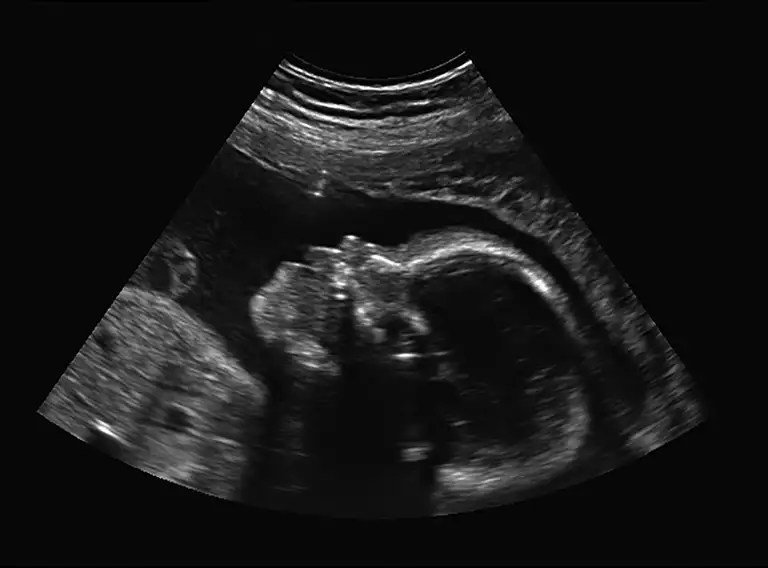

Det er muligt at diagnosticere og i nogle tilfælde behandle barnet allerede, imens det ligger godt og trygt i mors mave. Det er blandt andet derfor, at gravide kvinder får tilbudt nakkefoldsscanning i første trimester. Her kan man for eksempel se, om barnet har øget risiko for Downs syndrom, bugvægsdefekter eller andre bestemte misdannelser.

Et forældrepar får efter en scanning i uge 12 at vide, at lægerne mistænker, at deres foster mangler at udvikle et blodkar tæt på hjertet (DVA)*. Det bliver bekræftet ved en opfølgende scanning i uge 14, og deres ufødte dreng diagnosticeres med DVA.